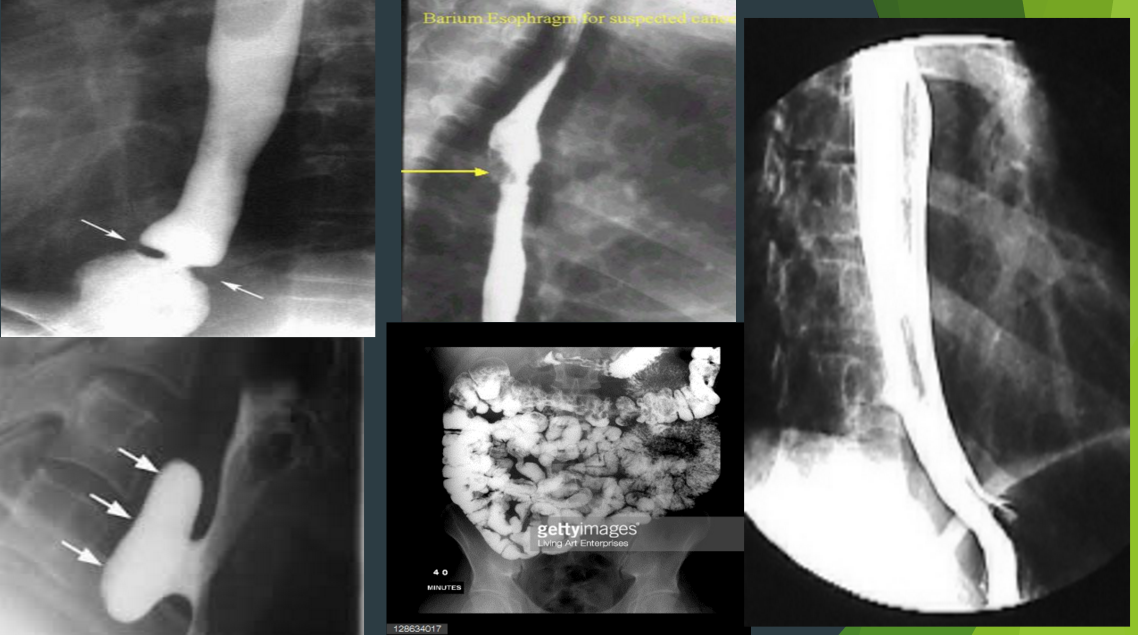

Indications for an Upper GI series?

4

Indications

Upper GI series contraindications?

Risk? 1

Contraindications

Risk